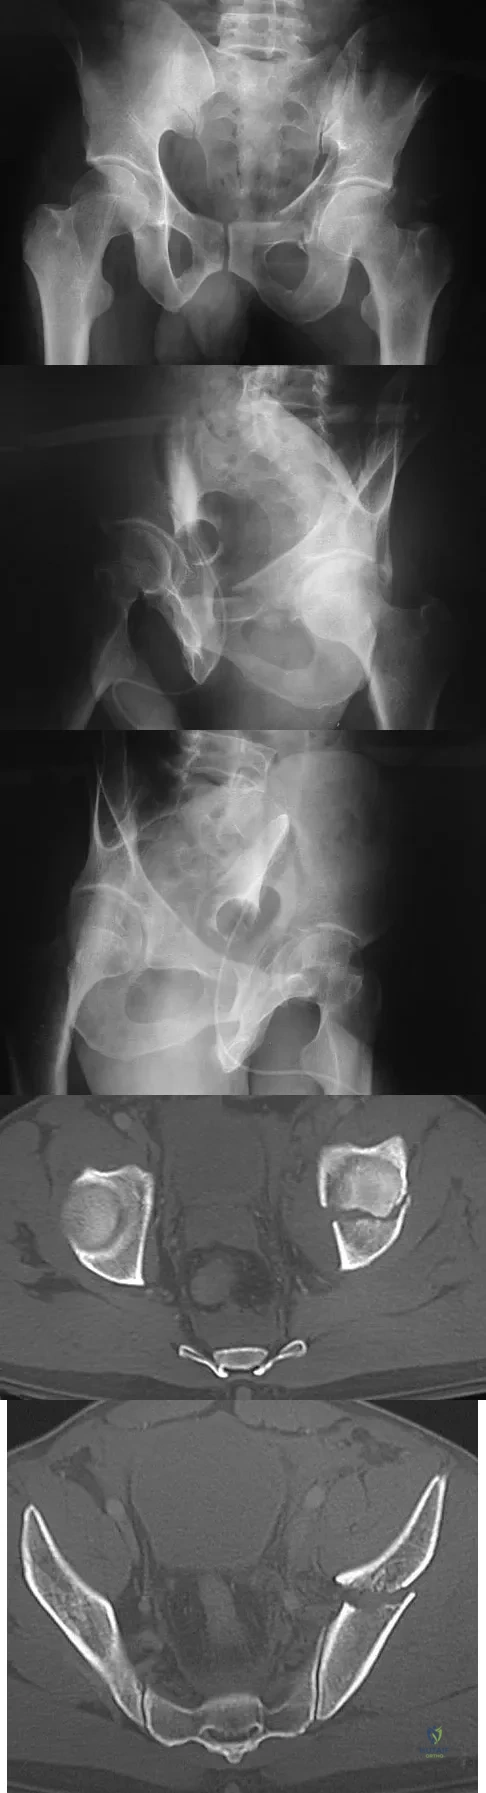

A 38-year-old woman fell from a ladder onto her right hip. The radiographs and CT scan are shown in Figures 52a through 52d. What is the best surgical approach for this fracture?

A 40-year-old laborer sustains the injury shown in the radiograph and CT scan in Figures 56a and 56b. What is the most common complication associated with surgical intervention?

A 24-year-old man is ejected from his motorcycle and sustains a significant hip injury. The fracture shown in Figures 64a through 64e is best described as what type of fracture?